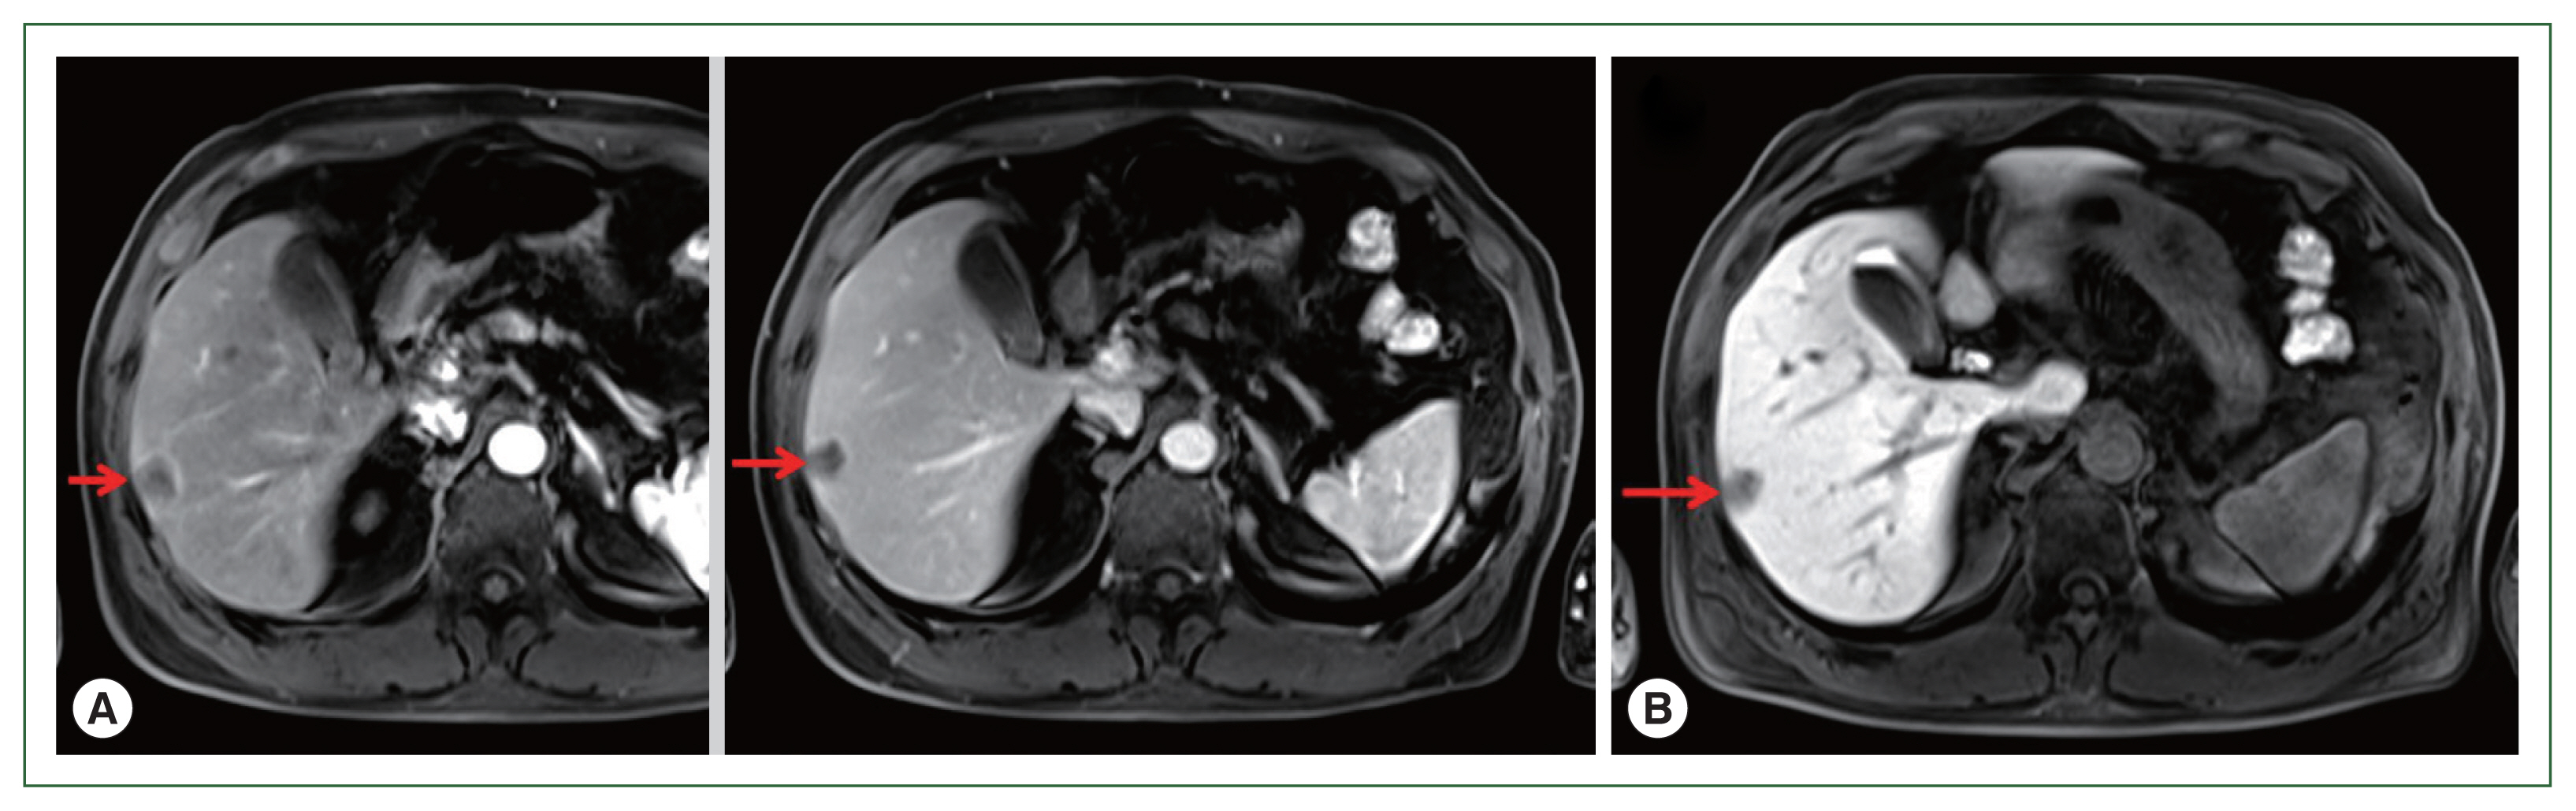

A 71-year-old male patient was admitted to Kyoto Prefectural University of Medicine Hospital with a liver tumor impression. He had a previous history of hypertension, gout, and prostatomegaly. He underwent appendectomy at 30 years of age. He had a family history of lung cancer, which affected his mother. Abdominal ultrasonography performed in health check-up revealed a low-density area of 20 mm in diameter in segment 6 of the liver. He was referred to our hospital for a more detailed lesion examination after 1 month. Difficulties were associated in reaching a definitive diagnosis although computed tomography (CT)-ethoxybenzyl-diethylenetriamine pentaacetic acid-enhanced magnetic resonance imaging (EOB-MRI) images were investigated (

Figs. 1,

2). Therefore, a liver biopsy was performed and tissue sections were examined. Preoperative diagnosis includes a liver tumor (S6), and a differential diagnosis from hepatocellular carcinoma, metastatic liver cell carcinoma, cholangiocarcinoma in the liver, and an inflammatory pseudotumor was required. Borderline-limited necrotizing granuloma comprising coagulation necrosis containing eosinophilic ghost cells and liquefactive necrosis with a desquamated cytoplasm was revealed in a pathological examination of a tissue section from a surgical sample obtained under laparoscopy. Necrotizing granuloma of the S6 lesion in the center of the tissue section was partially resected, revealing avascular necrosis in the cavity, and contained a necrotic larval nematode with a thick pellicle and amorphous content, indicating an anisakis infection (

Fig. 2(A) EOB-MRI. Left: Early stage of arterial phase. Right: Equilibrium stage of arterial phase. Arrows show a low-density area of 20 mm in size in segment 6 of the liver. (B) EOB-MRI. Liver cell phase of arterial phase. Arrow shows low-density signal regions that showed lighter color than those of the early and equilibrium stages. EOB-MRI, ethoxybenzyl-diethylenetriamine pentaacetic acid-enhanced magnetic resonance imaging.